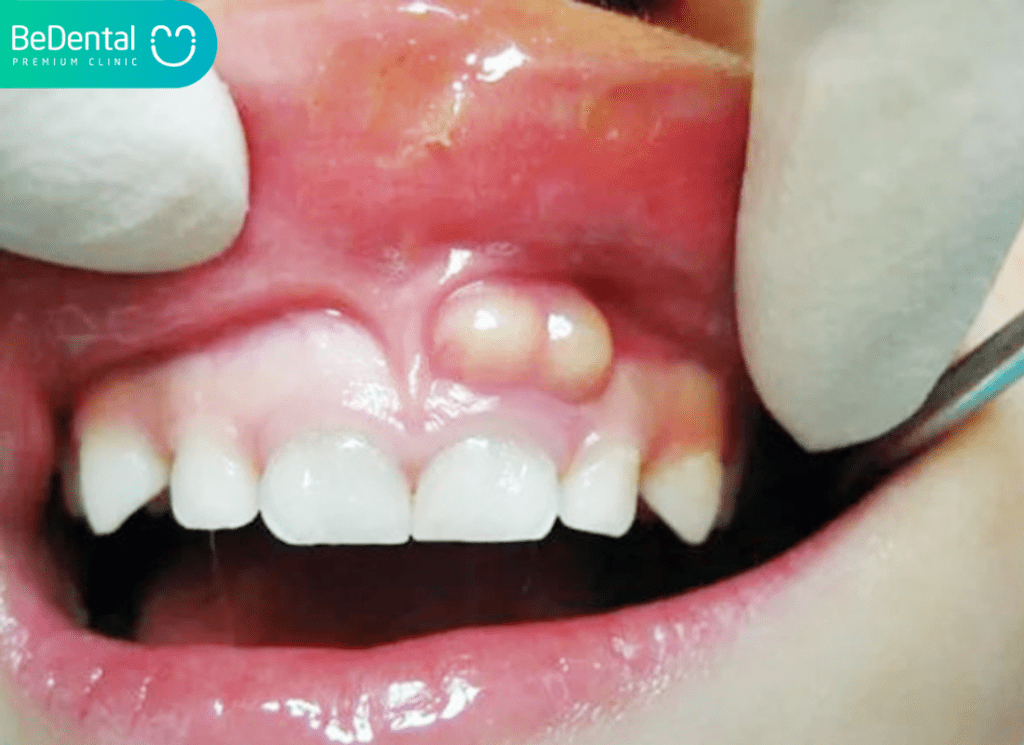

Viêm lợi trùm và Áp xe nướu răng:

Áp xe nướu răng là một dạng nhiễm trùng nghiêm trọng, xảy ra khi vi khuẩn xâm nhập vào mô nướu. Mặc dù áp xe thường gây đau nhức, nhưng trong một số trường hợp, áp xe đã phát triển lâu ngày có thể trở nên cứng và nổi cục trong miệng không đau, ẩn chứa nguy cơ nhiễm trùng lan rộng.